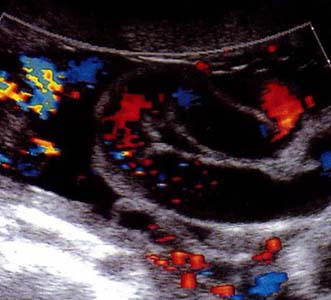

Mesure du DIO